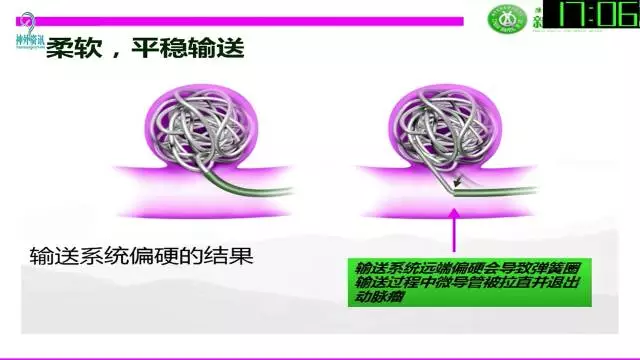

今天为大家分享的是“强生医疗CNV-神经介入专栏”第三十六期,由重庆第三军医大学附属新桥医院神经外科刘俊带来的“Galaxy弹簧圈在不规则动脉瘤中的临床应用”精彩讲课视频及PPT,欢迎观看。文章仅代表作者个人观点,如有不同见解,欢迎同道斧正!